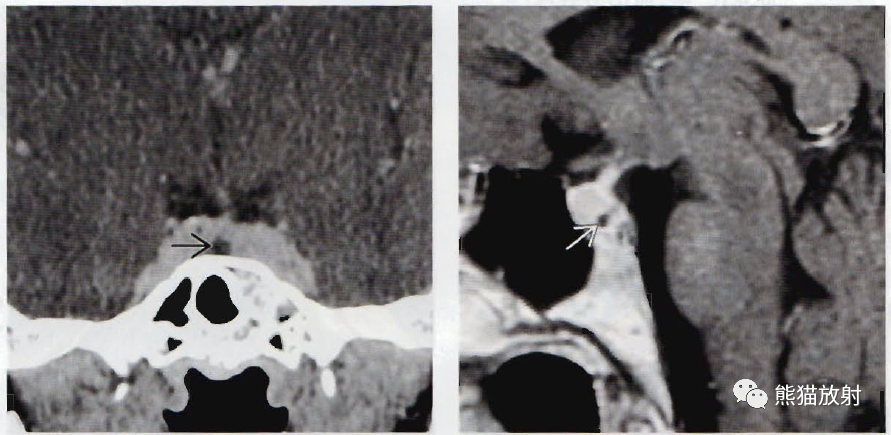

(左) 冠状位动态T1WI C+MR显示正常垂体强化。因垂体左侧的病灶比正常垂体强化慢,8mm的病变清楚可见。

(右) 动态增强后,冠状位T1WI C+MR显示病灶明显延迟强化。如果结节没有局部增大,在标准T1WI C+扫描上不能辨认。

(左) 一例无症状患者,冠状位CECT显示垂体内小的无强化灶。

(右) 同一患者,矢状位T1WI C+MR显示垂体轻度增大,CT扫描上的小病灶可见,无强化。在对比增强CT和MR扫描中,垂体“偶发瘤”常见。